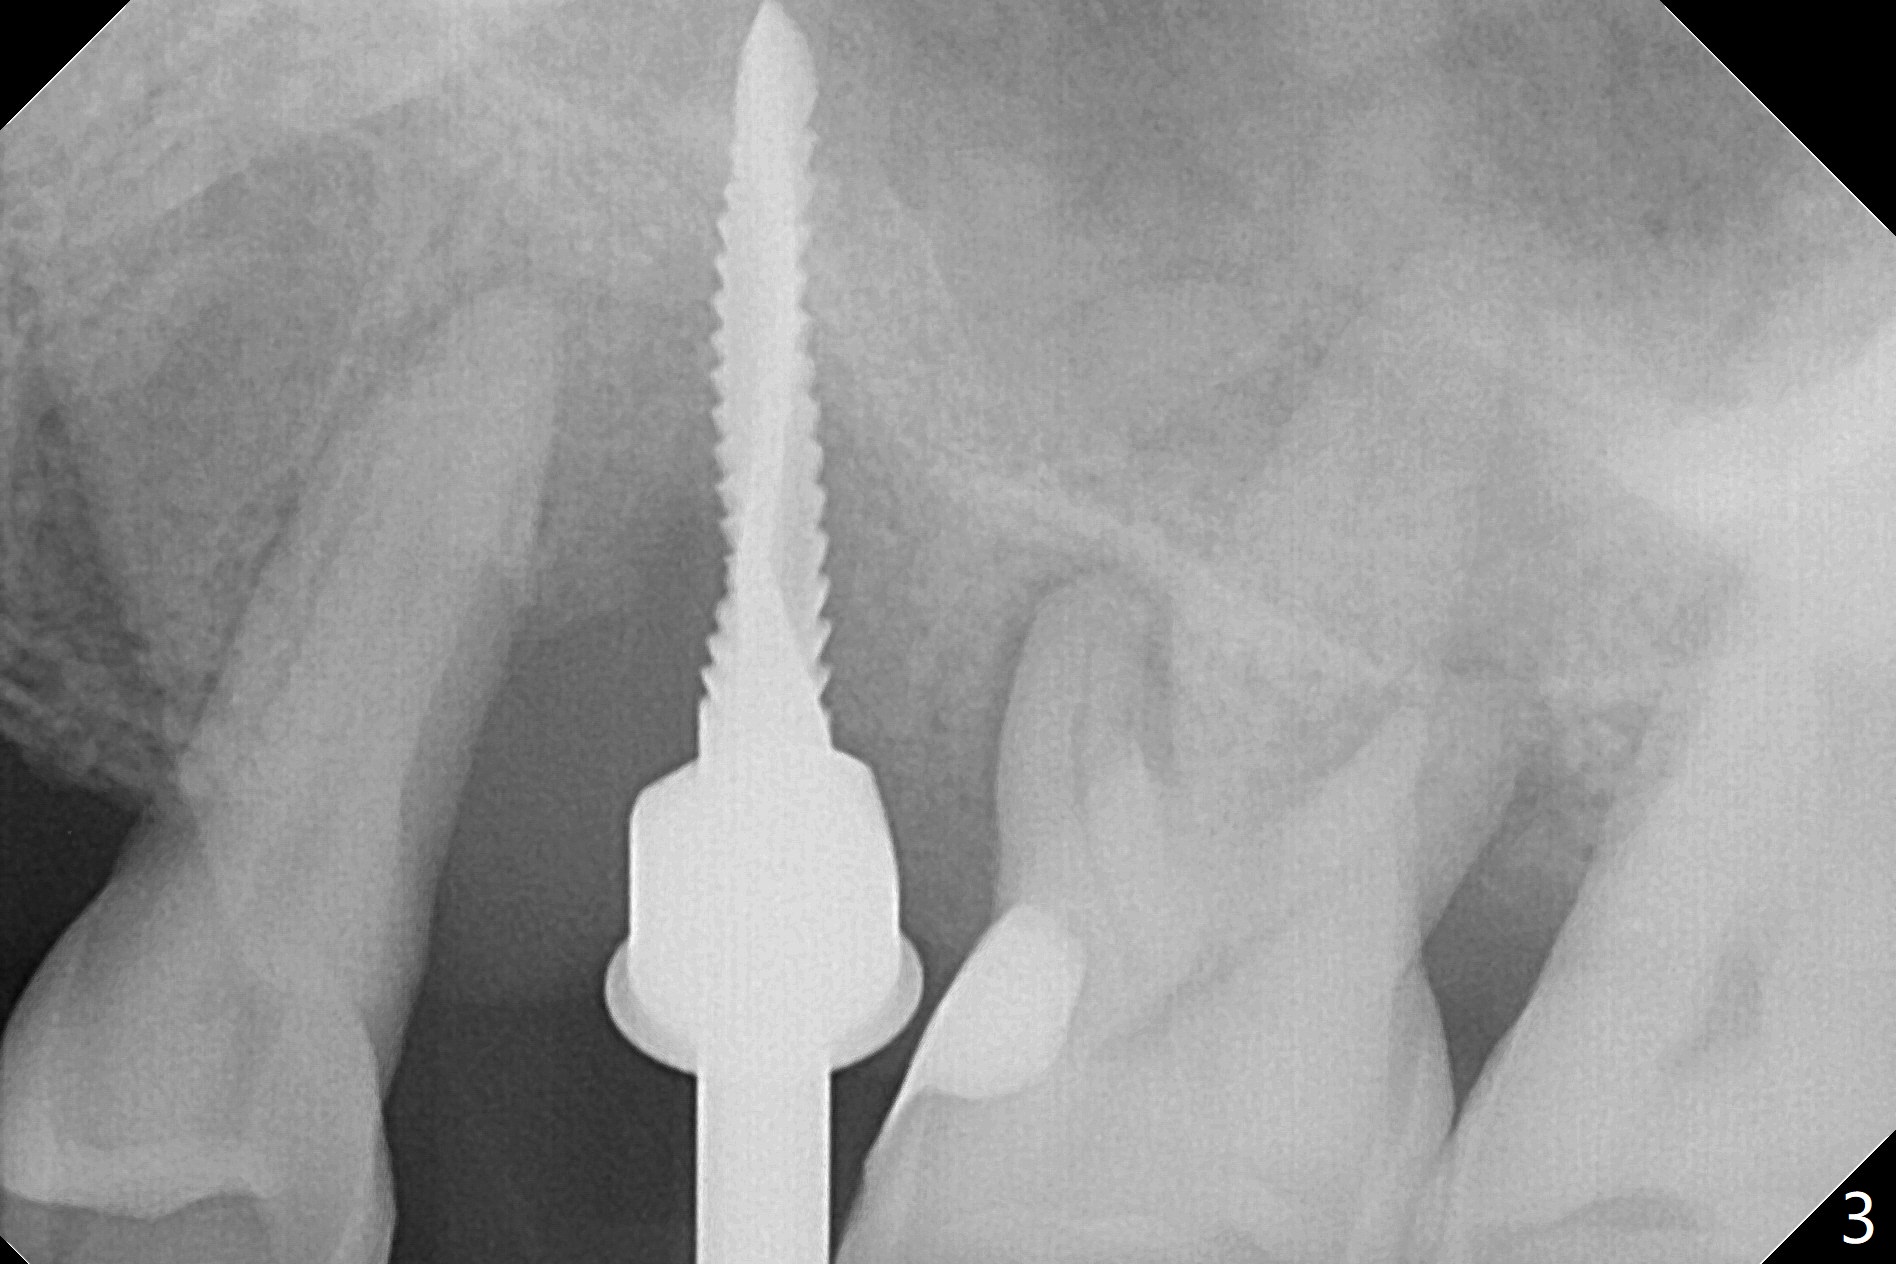

There is more bone apical to the residual root at #13 (Fig.1 red line). An immediate implant along the long axis of the root can be longer, 11.5 mm, favorable for primary stability (Fig.2 (CT taken immediately preop)). The initial trajectory is not ideal (Fig.3). When the pointed/Lindamann bur is removed (Fig.4), effort is made to move the apical end of the osteotomy distal (Fig.5 red arrow) by removing the apical bone (red dashed line). Following sequential osteotomy, a 4x10 mm dummy implant is placed with the trajectory remaining not so ideal (Fig.6,7). As the dummy implant is removed (Fig.8), a new osteotomy is established distal to the existing one (Fig.9). Subsequent drills gradually shift into the original osteotomy (Fig.10 red arrow). When the same dimension dummy implant returns, the trajectory improves with decreased stability (Fig.11). It seems reasonable to place a larger implant without further osteotomy. After placing PRF membrane and Vanilla graft for sinus lift (Fig.13 *), a 4.5x10 mm definitive implant is placed with loss of control in the trajectory (Fig.12,13).

When the initial osteotomy is off substantially (Fig.4), an osteotomy should be established de novo and as early as possible (Fig.14) so that subsequent osteotomy will not relapse to a great extent. More ideally, the initial osteotomy should be planned correctly (Fig.15,16) with sacrifice of the bone height. Nearly 1 month postop, the 4.5x5.5(5) cementation abutment is loose. When it is removed, the patient feels pain from the implant. A 5.5x6 mm healing abutment is placed instead. The implant osteointegrates with trabecular pattern in the sinus 9 months postop (Fig.20 *). The gingiva around the crown at #13 is healthy 1 year 4 months post cementation (Fig.18). Check the distal surface of #13 for bone loss if the tooth #14 is to be extracted.